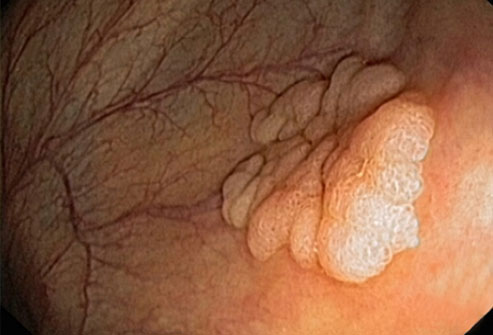

大多数结肠癌是大肠内壁生长的息肉发展而来的。息肉可能是也可能不是癌细胞。如果息肉属于癌细胞,那么癌细胞可能会扩散到身体的其他部位。在息肉癌变前就将其移除,可以完全预防结肠癌。

结直肠癌筛查